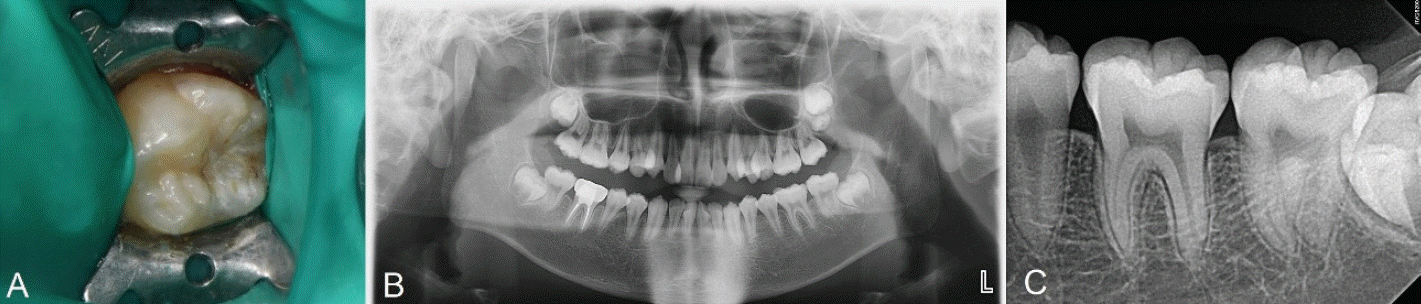

Fig. 4.

A. Selective etching iss done with 37% phosphoric acid. B. Stamp is placed and gently pressed. C. Photograph after applying stamp on teeth. D. Postoperative periapical radiograph.